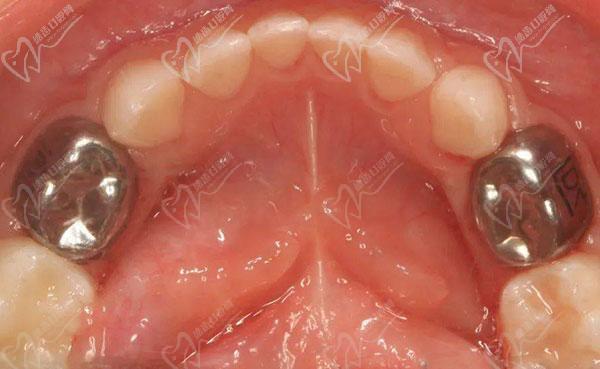

预成冠(也称为冠融合或预制冠)是一种牙科修复技术,用于恢复牙齿的形状和功能,多用于少年儿童口腔作为牙齿修复的一种牙冠。为了便于大家理解预成冠是什么意思,看以下预成冠图片告诉你预成冠是什么?通过了解以下预成冠的适应症和禁忌症可以帮你更好的保护好牙齿哦。

常见预成冠有金属预成冠、树脂透明预成冠。预成冠就是在乳牙大面积的龋坏或缺损、乳牙根管治疗后一般会为了保护乳牙采取的一种修复或者保护措施。

以下2种预成冠图片:

金属预成冠:

金属预成冠

金属预成冠通常会用于后牙,贴合的包裹后牙并保护牙齿,加强牙齿强度,保护恒压和乳牙能够正常替换。